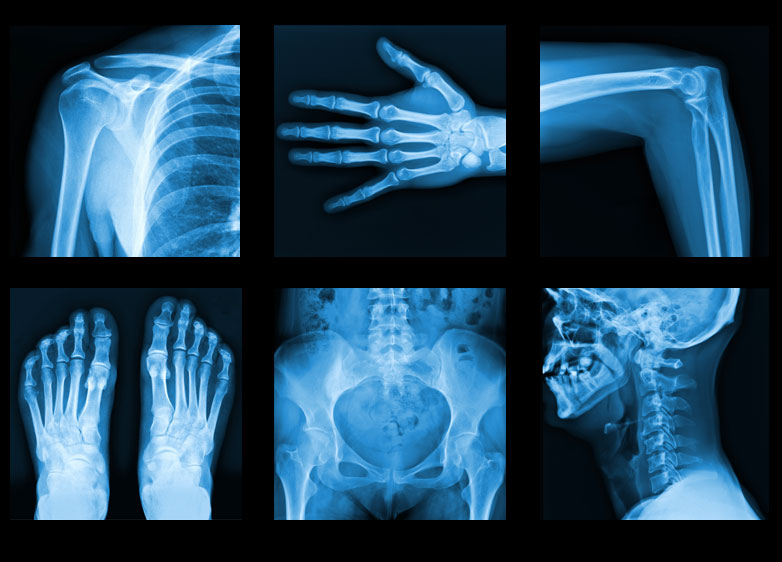

x – ray

x – ray Introduce : The meaning of the x-ray instrument that is one of the scientific instruments. Types of radiation used with x-ray instruments. The price of the x-ray instrument used as a medical tool.

Body 1 Is a scientific instrument by irradiating through the human body to be able to see within the body. Is a scientific tool that can diagnose many parts of the body such as shedding the body’s abnormalities Shedding the abnormalities of the teeth and shedding abnormalities within the system. Is a scientific tool by using electrical waves to maintain the internal system of the body.

Body 2 There are 2 types of radiation used in treatment. X-rays with continuous spectrum is the X-ray obtained from the X-ray generator by accelerating the charged particles into the metal target. X-rays with unique spectrum Or unique X-rays is a X-ray that is derived from the decay of radioactive elements which is stimulated by energy from within the atom.

Conclusion X-ray tool Is a scientific tool by irradiating through the human body so that it can be seen within the body. There are 2 types of radiation used in the treatment namely X-ray with continuous spectrum and X-rays with special spectrum. There is a relatively high cost of treatment so take care of yourself to stay healthy all the time.